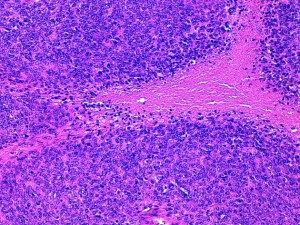

- L’IM doit être le nombre de mitoses pour 10 HPF (x400) mesuré dans la portion la plus cellulaire de la tumeur et la plus mitotique. Si le nombre atteint est proche du seuil il faut recommencer pour confirmer le score obtenu. On doit éviter les zones nécrotiques, hypocellulaires ou ulcérées (Fig 1).

- La nécrose doit être différenciée des remaniements mucineux, hyalins, hémorragiques ou traumatisés par la chirurgie ou la technique biopsique (Fig 2)